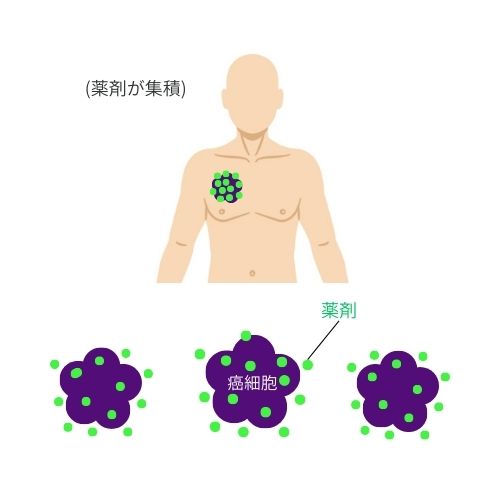

➂ 薬剤を保持

薬剤点滴後、保持する事でがん細胞に薬剤が集積します。がん細胞に薬剤が集積するため、がん細胞のみを攻撃する事ができます。これが副作用が少ない理由です。※当日薬剤点滴から照射も可能です。